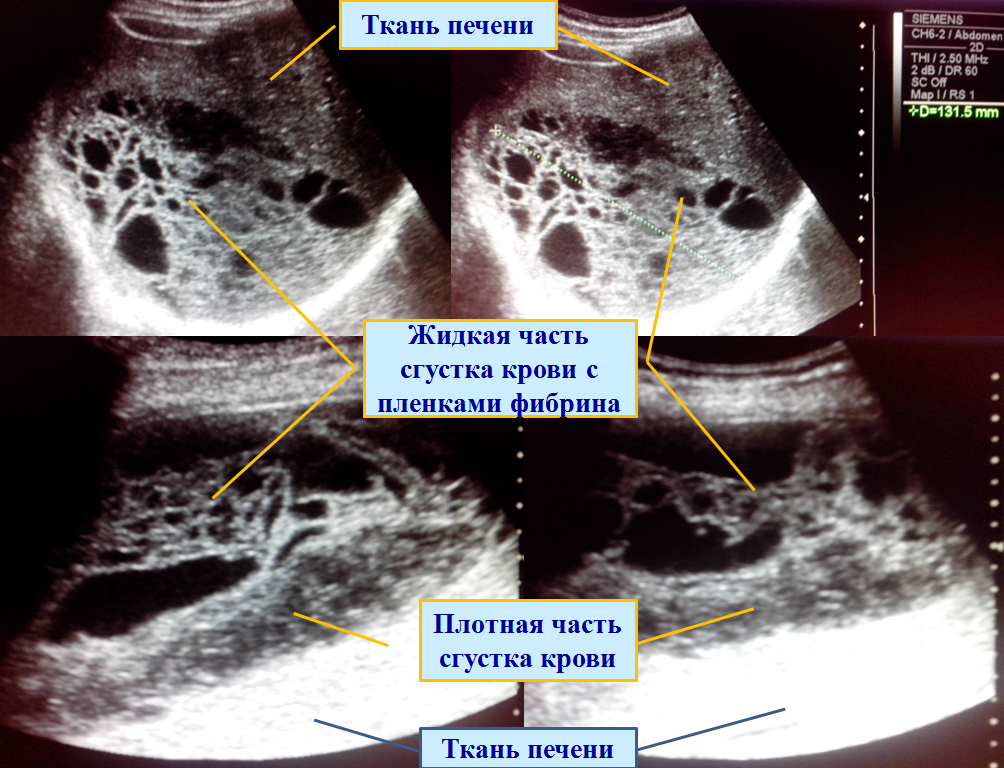

Сложность представляет внутрибрюшная гематома, особенно, если отсутствуют указания на травму в анамнезе.

Только при беглом общем осмотре картина кажется характерной для эхинококка.

Но! При детальном рассмотрении видно, что ячейки «дочерних кист» имеют неправильную форму, значительно разнятся по диаметру, перегородки – стенки «дочерних кист» колышутся в такт дыхания или сердцебиения, базальная часть данного образования представлена массивной плотной частью без жидкости и перегородок (плотная часть сгустка крови).